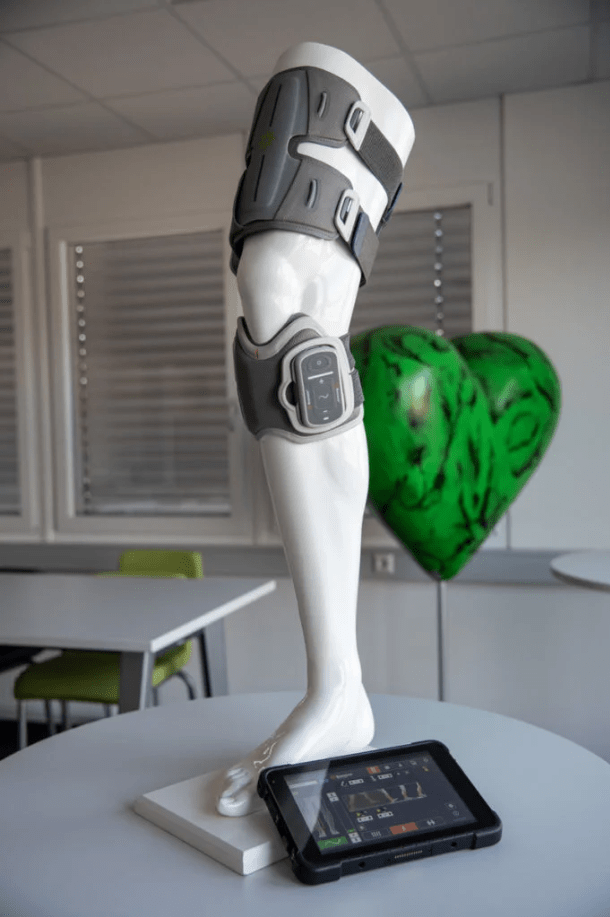

پروتزهای عصبی حرکتی با تحریک الکتریکی عملکردی (FES) نوعی فناوری پزشکی هستند که برای بازگرداندن عملکرد حرکتی به افرادی که به دلیل آسیب به سیستم عصبی مرکزی مانند آسیب نخاعی یا سکته، توانایی حرکت خود را از دست دادهاند، استفاده میشوند. این پروتزها با استفاده از الکترودهایی که به اعصاب یا عضلات مرتبط با حرکت متصل میشوند، سیگنالهای الکتریکی را به بافتهای هدف ارسال میکنند. این تحریک الکتریکی باعث انقباض عضلات و در نتیجه ایجاد حرکت میشود. هدف اصلی این پروتزها، بهبود کنترل حرکتی و افزایش استقلال بیماران در انجام فعالیتهای روزانه است.یکی از مثالهای بارز این نوع پروتزها، فوت دراپ (Foot Drop) است که در آن فرد نمیتواند بهدرستی پا را در هنگام راه رفتن بلند کند. در این حالت، پروتزهای FES میتوانند با تحریک الکتریکی عضلات جلوی ساق پا، حرکت طبیعی بلند کردن پا را شبیهسازی کنند. از دیگر مثالها میتوان به تحریک عضلات بازو برای کمک به بیماران دچار سکته جهت بازگرداندن کنترل در حرکات دست و بازو اشاره کرد. این تکنولوژی همچنین در بازتوانی بیمارانی که دچار ضعف عضلانی هستند، بسیار کاربردی است.